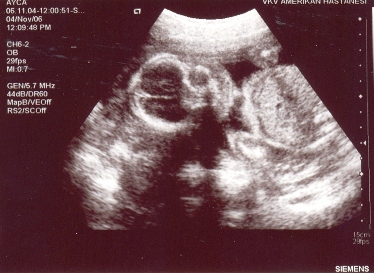

Bugün kontrole gittik sonunda teknolojiye yenildim:)gerçekten öğrenmek istemeseydim bile görücekmişim pek kaçırılacak bir görüntü değil, hoş ben hala kalbine koluna parmaklarına bakmaktan pek anlayamadım ama Alpay pek kaçırmamış: “şu balon gibi yukarı çıkan şey pipisi mi ? “dedi….benim anlamam için bütün görüntüyü geri sarmak gerekti.. sonunda gördüm,şu an alttaki görüntüde bilmem benden başka kimin anlayabileceği bir pipisi var çocuğumunnnnn:)

İlk görüntüde ise ayak parmakları,ikinci görüntü önden yüzünün görünüşü.

456gr olmuş 🙂